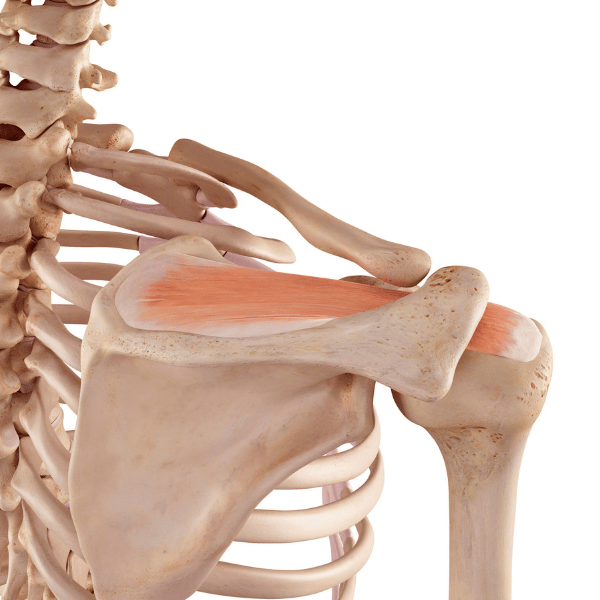

- Rama

Izpah rame: ključne informacije in kako poteka rehabilitacija

Do izpaha rame pride, ko se glavica nadlahtnice premakne iz...Izpostavljeno

Sindrom zamrznjene rame

Zamrznjena rama je stanje zmanjšane gibljivosti in bolečine v ramenskem...

Utesnitveni sindrom rame

Utesnitveni sindrom rame sodi med najpogostejša bolečinska stanja v ramenskem...Izpostavljeno